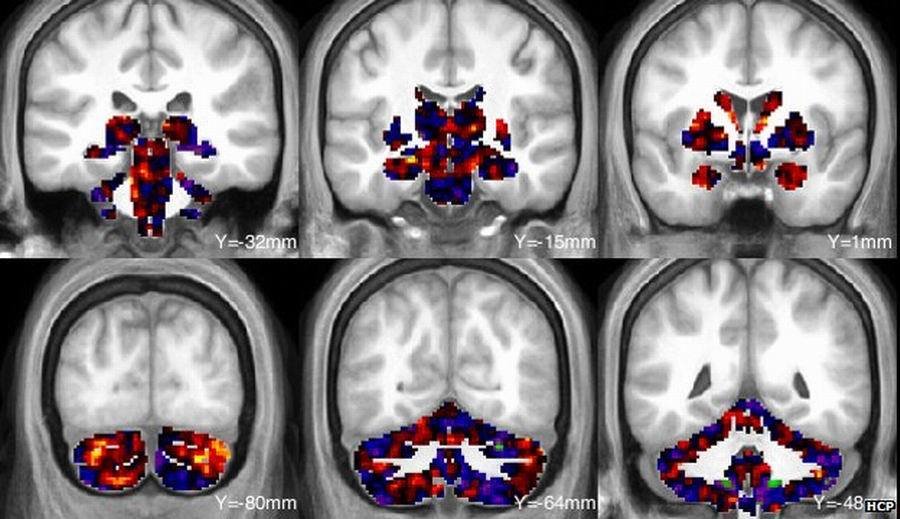

灰色影子:大脑灰质中的大脑活动,当志愿者观看人类面孔时黄色和红色

图片说明:图中蓝色区域为大脑灰质.